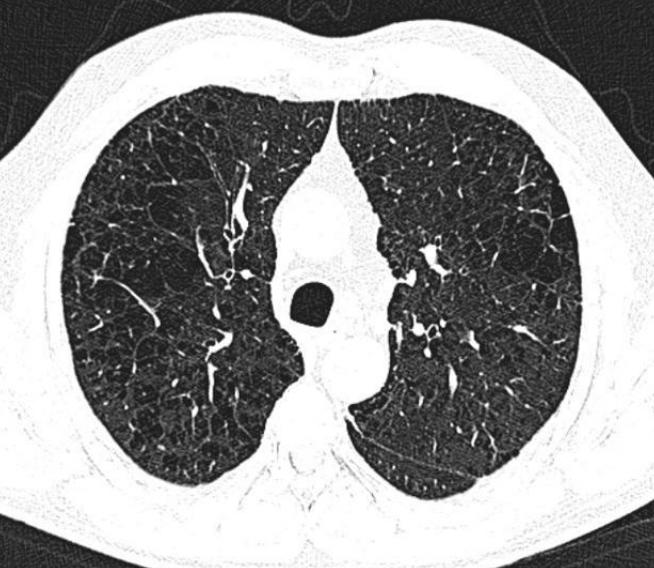

TAC

Permite clasificar: centrolobulillar, panlobulillar, paraseptal